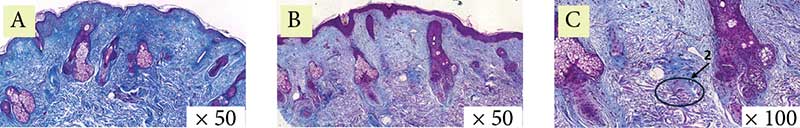

Рис. 2. Пациентка 1. Окраска по Ван-Гизону: A – до процедуры, B и C – через месяц после процедуры (стрелка указывает на участок упорядочения и структуризации коллагеновых волокон)

Рис. 3. Пациентка 1. Окраска по Массону: A – до процедуры, B и C – через месяц после процедуры (стрелка указывает на участок упорядочения и структуризации коллагеновых волокон)

Гистологически в эпидермисе отмечается уменьшение гиперкератоза, сглаживание эпидермальных гребней. В дерме отмечены выраженные лимфоцитарные инфильтраты, что свидетельствует о незавершенном воспалительном процессе, а также единичные участки с увеличенным количеством упорядоченных коллагеновых волокон, что говорит о начале и продолжении синтеза коллагена и его реорганизации. Признаков фиброза не отмечено (рис. 1–3).